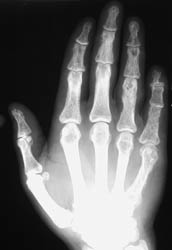

The hands are the most common site of osseous involvement. The middle and

distal phalanges and less frequently the proximal phalanges and metatacarpals

may show changes associated with sarcoidosis. Involvement at the wrist occurs

much less frequently.

An abnormal trabecular lace-like pattern of destruction can often be seen

at the phalanges and metacarpals of the hands. Cystic changes and osseous

destructive lesions may also be evident. Acro-osteosclerosis with the radiographic

appearance of terminal phlangeal sclerosis is not specific; however, it has

been reported in up to half of the patients with skeletal abnormalities of

sarcoidosis. Soft tissue swelling, and inflammatory skin nodules (erythema

nodosum) are occasionally noted. If the wrist is involved, cystic changes

and lytic lesions may be present.